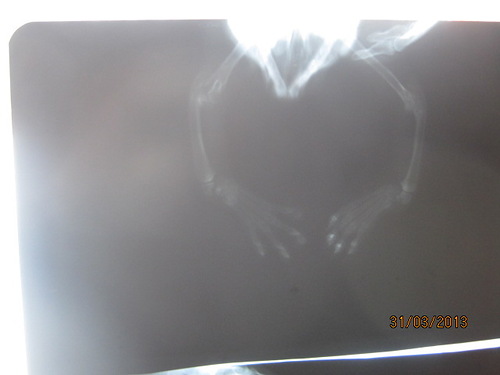

СЕЙЧАС ЗАГРУЖУ все. правда плохо видно-солнце слепило в окно(

во вторник со снимками поедим к хирургу-получим назначения-пока только Циклофирончик сказали поколоть и в ушках клеща немного.

Отсутствие лучевой кости на лапах!!! Кости вообще НЕТ!!!

Что будет дальше и как он сможет жить - никто не знает.

Мне кажется, что лучевая кость - это не жизненноважный орган. Единственное, с ручками надо быть оооооооооооочень избирательными, так как в момент роста (а кости тоже растут) придётся ребёнка ограничивать в подвижности... Живут же люди с культями и т.д... Главное, чтобы костяк сформировался . Кстати, а у кошек как нагрузки распределены между задними и передними лапами???

Ещё вопрос по строению суставной сумки, тк в норме к ней 2 кости прикреплены, а тут одна... - как бы не было частых вывихов и скопления суставной жидкости.

Он до сих пор жив и ходит. По отзывам Катрин довольно шустро. Значит можно надеяться на компенсацию недостающей кости, перераспределением функций органов движения, главное, чтобы не было травм. Он очень смешно в клетке сидел - как зайчик, столбиком, очень необычно, видимо это часть компенсации.